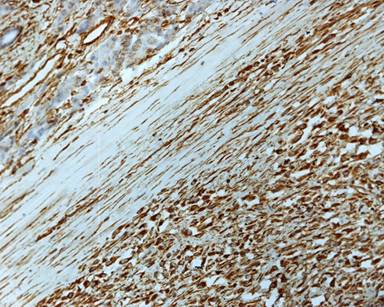

A 11-year-old male presented with complaints of painless hard swelling involving left lumber, umbilical and left hypochondrium of abdomen. According to his mother he was apparently asymptomatic 20 days back when he incidentally noticed firm to hard swelling in left upper abdomen. No history of fever, vomiting, jaundice, weight loss and hematemesis and bleeding per rectum was seen. No family history of a genetic disease was seen. Clinical examination was normal. Body fluid amylase was 4,800 U/L (reference range: 4-234 U/L) and liver function tests were normal. Computed tomography (CT) revealed a large mass measuring 10.0x8.8x7.5 cm in the pancreatic tail, mainly solid but small cystic component (Figure 1). The pancreatic tail mass was well-delimited but not encapsulated. There was no evidence of local invasion or metastasis. The surrounding vessels (celiac trunk, superior mesenteric artery, and splenic and portal veins) were not invaded. The surrounding pancreas was normal. The clinical diagnosis of adenocarcinoma of the pancreas was suspected. Resection of pancreatic tail mass and distal pancreatectomy with splenectomy was performed. Operative findings showed a mass with cyst involving pancreatic tail, adherent to splenic vein and artery, free from stomach and left kidney. The macroscopic examination revealed compressed pancreas measuring 4.0x1.0x0.5 cm, spleen measuring 8.5x6.0x3.5 cm with mesentery measuring 3.0x3.0x0.5 cm. and a well circumscribed, non-encapsulated, dense, mesenchymal tumor measuring 10.0x8.8x7.5 cm with a cystic area measuring 1.5 cm in diameter (Figure 2). Outer surface of the tumor was grey white and lobulated. No lymph node was seen. Histological examination showed a circumscribed tumor arranged in intersecting fascicles infiltrated the surrounding pancreatic parenchyma (Figure 3).Tumor cells are mildly anisomorphal with spindle shaped cells having elongated nuclei with blunt ends and bipolar cytoplasm. Mitosis is infrequent (less than 1-2 per 10 high power fields). Necrosis was not seen. Spindle shaped cells have a regular nucleus and were separated by large amounts of collagen fibers in edematous tissue with some inflammatory cells (Figure 4). The cystic component was seen within the tumor. Spleen showed congestion and focal fibrosis. Immunohistochemical analysis revealed that the tumor cells were strongly positive for beta-catenin (Figure 5), vimentin (Figure 6) and negative for cytokeratin (CK), CD34 (Figure 7), S100, CD68, CD117, smooth muscle actin (SMA) (Figure 8), muscle specific actin, desmin, CD99, Bcl2, anaplastic lymphoma kinase 1 (ALK-1) and human melanoma vlack 45. Proliferation marker Ki67 stained about 2% of the tumor cells. The immunohistochemistry and histopathological features were consistent with a confirmed diagnosis of desmoid tumor. A short term follow-up showed rapid disappearance of the symptoms which had revealed the desmoid tumor. Because of complete resection and the sporadic origin of the desmoid tumors, no corresponding treatment was given. After 10 months of follow-up, the patient is well and normal on clinical examination.

Figure 5. Tumor cells are strongly positive for beta-catenin immunostaining (x40 magnification). |

Figure 6. Tumor cells are strongly positive for vimentin immunostaining (x40 magnification). |